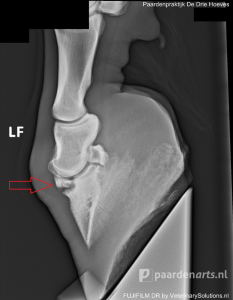

Letsel

Wanneer de ernst van het letsel niet met zekerheid vastgesteld kan worden aan de hand van regulier onderzoek, kan er een röntgenfoto gemaakt worden. Bijvoorbeeld bij verdenking van een botbreuk (zie foto).

Bij kreupelheidsdiagnostiek wordt het paard nauwkeurig onderzocht. Röntgenonderzoek kan helpen om bepaalde aandoeningen of oorzaken aan het licht te brengen. Bij kreupelheidsdiagnostiek kan bijvoorbeeld middels röntgenbeelden gewrichtsartrose zichtbaar worden evenals een ontsteking aan het botvlies, hoefkatrolontsteking, fracturen, scheurtjes etc.